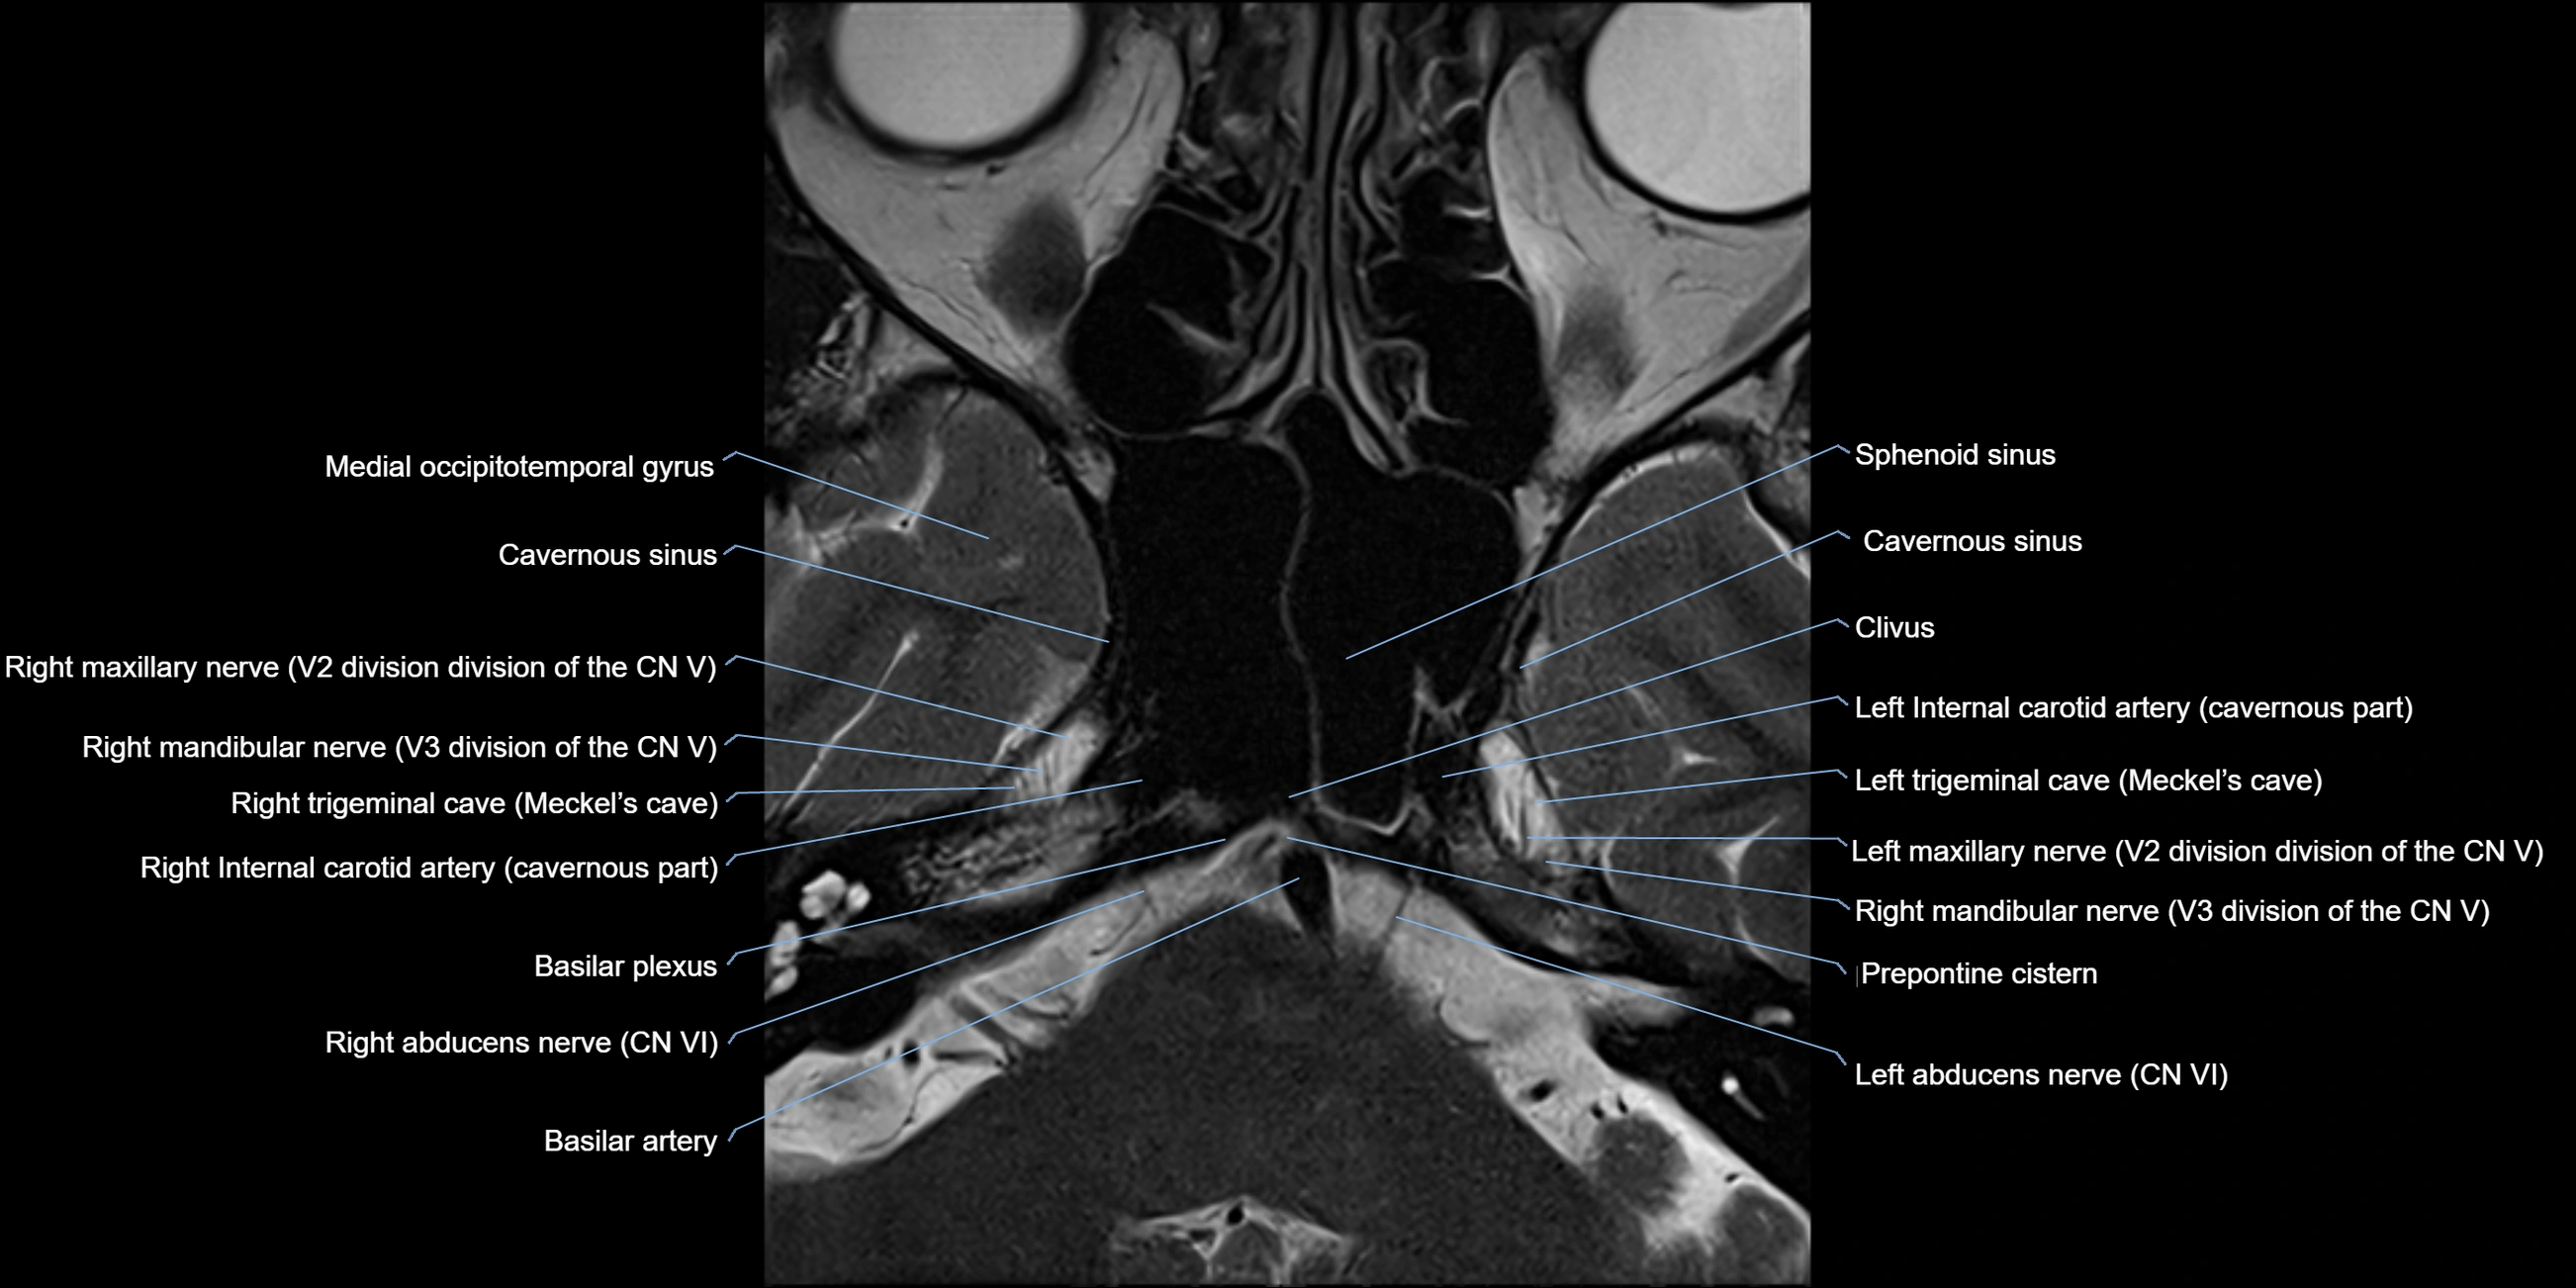

MRI Appearance

-

The abducens nerve is a small, thin, linear structure

Best visualized on high-resolution T2-weighted 3D MRI sequences (e.g., FIESTA or CISS)

Seen as a hypointense (dark) line running from the brainstem at the pontomedullary junction, traversing the prepontine cistern, and entering Dorello’s canal under the petrosphenoidal ligament, then into the cavernous sinus, and finally the orbit

May be challenging to visualize in standard MRI due to its small size

Pathology may be inferred by absence, displacement, or enhancement of the nerve

MRI images